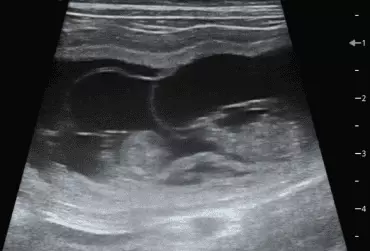

W literaturze opisano niewiele przypadków ciąż bliźniaczych jednokosmówkowych u suk. W trakcie wczesnej diagnostyki ultrasonograficznej ciąży u suki rasy whippet (chart angielski) zobrazowano pęcherz ciążowy, w którym znajdowały się dwa zarodki. Podczas badań kontrol­nych zarodki, a później płody wykazywały prawidłową organogenezę i żywotność. Ich rozwój przebiegał podobnie względem pozostałych ośmiu płodów. W 63. dniu ciąży wykonano zabieg cesarskiego cięcia i wydobyto dwa płody tej samej płci, o bardzo podobnym wyglądzie, z dwóch pęcherzy płodowych przyczepionych do jednego łożyska, oraz pozostałe osiem płodów.